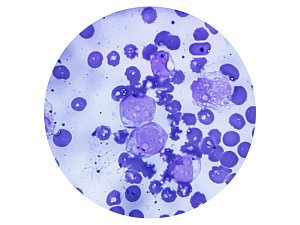

Целиакия (глютеновая энтеропатия) обусловлена развитием иммунной реакции по отношению к глутамин- и пролиннасыщенным глютеновым белкам. Содержание этих белков максимально в пшенице, ржи, овсе и ячмене.

Болезнь проявляется в любом возрасте: от младенчества до пожилого. Иногда в отсутствие клинической симптоматики обнаруживают циркулирующие антитела к тканевой трансглутаминазе (тТГ), играющую важную роль в патогенезе заболевания, что рассматривают как целиакию с латентным течением.

Признаками заболевания являются синдром мальабсорбции, сопровождающийся диареей и снижением массы тела. Часто развивается железодефицитная анемия, повышен риск развития остеопороза. Пациенты предъявляют жалобы на боли в животе, утомляемость, неврологические расстройства. В редких случаях отмечается наличие герпетиформного дерматита. При целиакии в отсутствие надлежащего лечения повышен риск развития неоплазий.

Диагноз устанавливается путем серологического исследования (при обнаружении циркулирующих антител к тТГ) и ЭГДС с биопсией дуоденальной слизистой для подтверждения субтотальной атрофии сосочков и лимфоидной инфильтрации.